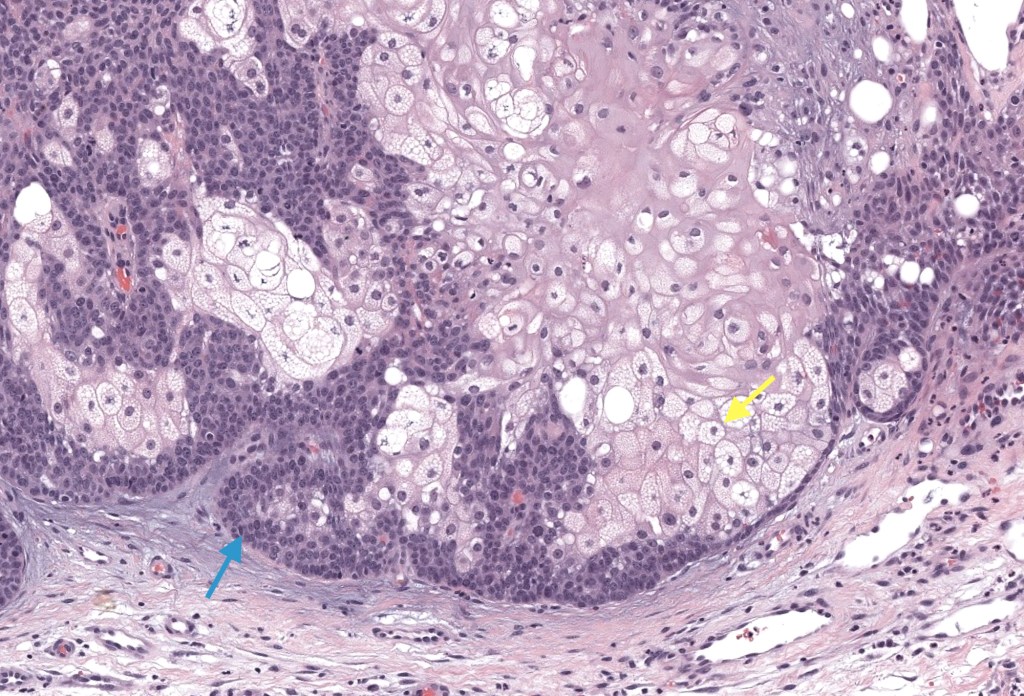

Histología: lóbulos con periferia basaloide y centro de sebocitos maduros; >50% sebocitos. Shalin 2010.

IHQ clave: adipofilina (+); AR/EMA de apoyo; MMR si factores de riesgo de SMT. Ostler 2010, Lee 2017.